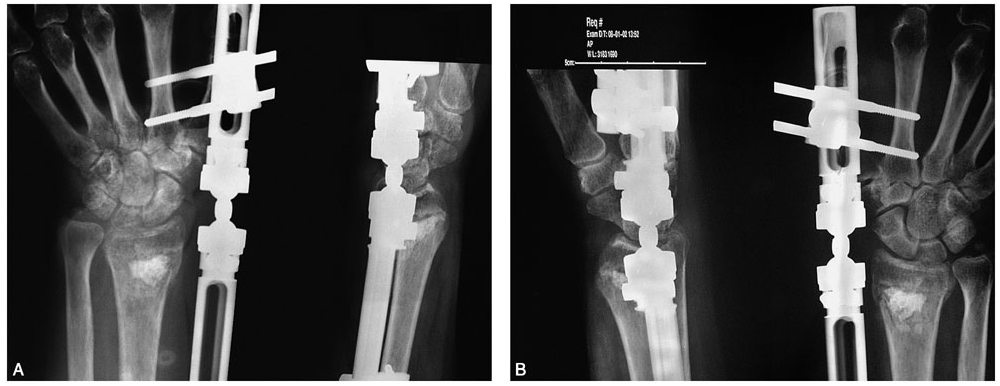

患者,女,51岁。因右腕摔伤后肿痛、畸形、活动受限,急诊就诊诊断为右桡骨远端骨折。行闭合牵引复位,石膏托外固定。拍片复查,桡骨远端背侧因骨折的粉碎性质而缺损巨大,背侧的皮质骨碎片向远端移位至桡腕关节间隙水平并嵌于腕背软组织中无法闭合复位(图2-1)桡骨远端背侧因缺乏可靠的皮质骨支撑而存在骨折继发移位、掌倾角向背侧倾斜且移位的皮质骨碎片潜在刺激背侧软组织、磨损伸肌腱的风险,增加发生关节疼痛和功能障碍的可能性,于是行桡骨远端骨折切开复位,人工骨植入,超关节外固定架固定术。

图2-1 桡骨远端背侧因骨折的粉碎性质而缺损巨大,背侧的皮质骨碎片向远端移位至桡腕关节间隙水平并嵌于腕背软组织中无法闭合复位

桡骨远端不稳定骨折是主要的手术指征,包括:①桡骨远端背(掌)侧皮质粉碎,关节面移位>2mm;②掌倾角向背侧倾斜超过20°~25°;③桡骨短缩> 5mm;④复位后不稳定,易发生再移位。骨折在纵向牵引下骨折块复位困难,骨折端的骨皮质支撑不满意,在骨折端夹有肌腱或骨膜。对于严重的关节内粉碎骨折,桡骨短缩明显,内固定螺钉无有效固定位置的病例,外固定架固定是首选方法。如Frykman分型中的Ⅶ、Ⅷ两型,通用分类法中的Ⅱ、ⅣA、ⅣB型,关节内四部分骨折等首先应考虑外固定架。此患者桡骨远端背侧皮质粉碎,复位后不稳定,易发生再移位。腕背侧移位的骨片闭合复位很难达到满意的位置。